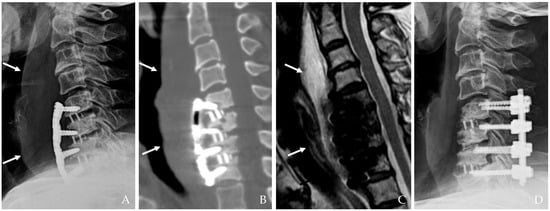

Figure 2. The patient underwent C5-6-7-T1 anterior cervical discectomy and fusion. At postoperative 6 days, postoperative infection occurred with retropharyngeal abscess and mediastinal extension (white arrows) (AC). Therefore, the patient underwent evacuation of retropharyngeal abscess, irrigation/debridement, removal of plate/screws, and C5-6-7-T1 posterior fixation and achieved a cure for the infection (D).

The infection may extend into deeper cervical tissues, forming abscesses that can coalesce and spread into the mediastinum. This is a life-threatening complication characterized by diffuse inflammation, tissue destruction, and multi-organ involvement (Figure 2) [10,12,14]. The time from surgery to abscess formation ranges from several days to weeks, and symptoms may include persistent fever, chest pain, and respiratory compromise.